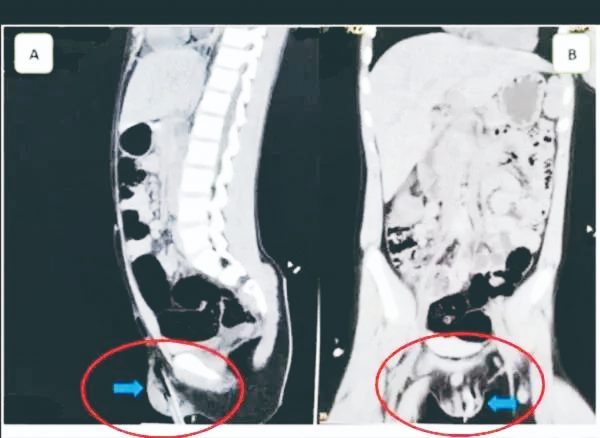

(印尼3日讯)日前在印尼锡江(Makassar)发生一起恐怖的意外事件,有一名11岁男孩爬上大树玩耍,没想到却不慎失足摔落,导致左侧阴囊被5公分的树枝刺穿。

媒体报导,患者的左侧阴囊下半部遭树枝刺穿,甚至可以碰触到耻骨,经医师检查过后,幸好睪丸没有受伤,便赶紧将异物移除,并且施打破伤风疫苗、服用抗生素药物,以避免伤口感染,而目前该男孩已经完全康復,仅需定期回院检查伤口。

然而,此意外事件也被英国皇家外科医师学会(RCSENG)成员、泌尿外科顾问医师格拉斯(Jonathan Glass)发表成一则医学期刊,并说明阴囊和睪丸的刺穿伤非常罕见,但“如果异物进入腹部,膀胱、大小肠、大动脉和静脉等器官都很危险”,万一受伤恐怕造成终身影响。(泰国世界日报)